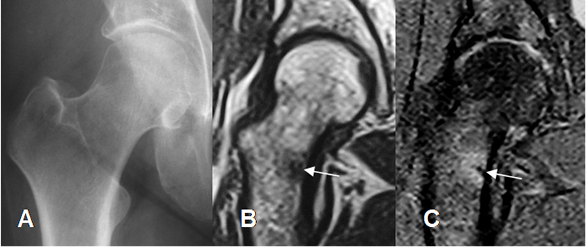

Fig 41. Fractura de stress.

A: Rx AP, sin cambios patológicos.

B: RM coronal en T1 y C: RM coronal en STIR. Fractura de stress en la parte medial del cuello femoral, vista como imagen hipointensa en ambas secuencias y con edema asociado.